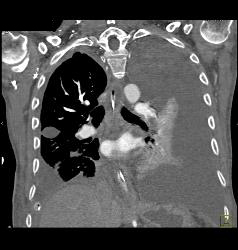

Diagnosis

Multiple Pulmonary Emboli (PEs)